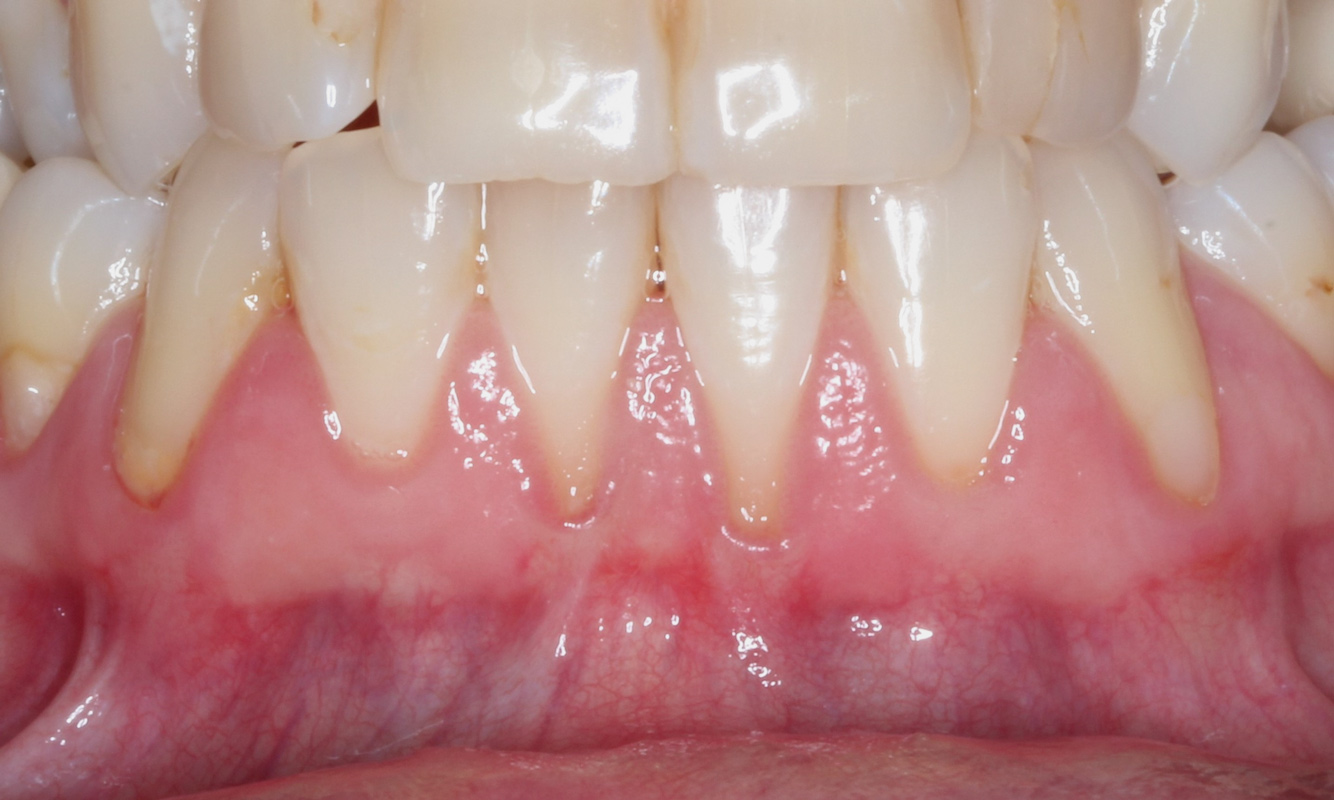

Fig 16. Miller Class I recession on teeth Nos. 24 and 25 (Fig 16) treated with a properly thinned tuberosity graft to 1.5 mm for complete root coverage grafting on teeth Nos. 23 through 26 (Fig 17). Note there is no keloid-like appearance on the graft.

Figure 16

Fig 17. Miller Class I recession on teeth Nos. 24 and 25 (Fig 16) treated with a properly thinned tuberosity graft to 1.5 mm for complete root coverage grafting on teeth Nos. 23 through 26 (Fig 17). Note there is no keloid-like appearance on the graft.

Figure 17

Dense CT presumably is less susceptible to shrinkage than less-dense CT. One problem with denser CT may be the need for a longer amount of time to blend in with adjacent non-grafted areas. Due to density, a CT graft might never completely blend in and always demonstrate an unesthetic keloid-like appearance. Therefore, with tuberosity tissue, adjusting the tissue thickness prior to placement of the graft is highly clinically relevant. This may be why periodontists have been reluctant to use tuberosity tissue as CT. Palatal tissue has less-dense CT than tuberosity tissue and, therefore, the authors hypothesize and have observed, shrinks more. Because palatal tissue has been the predominant tissue used in CTG, clinicians have become used to the shrinkage associated with the palatal CT and may not realize the need to thin a dense CTG to prevent a keloid-like appearance. Thus, in the past when a tuberosity was used for this purpose, if it was not properly trimmed it would have frequently resulted in an unesthetic keloid-like appearance. The tuberosity CTG should be trimmed to 1 mm to 1.5 mm thick to avoid the need for a future procedure to adjust tissue thickness for esthetics (Figure 3 and Figure 4, Figure 16 and Figure 17).